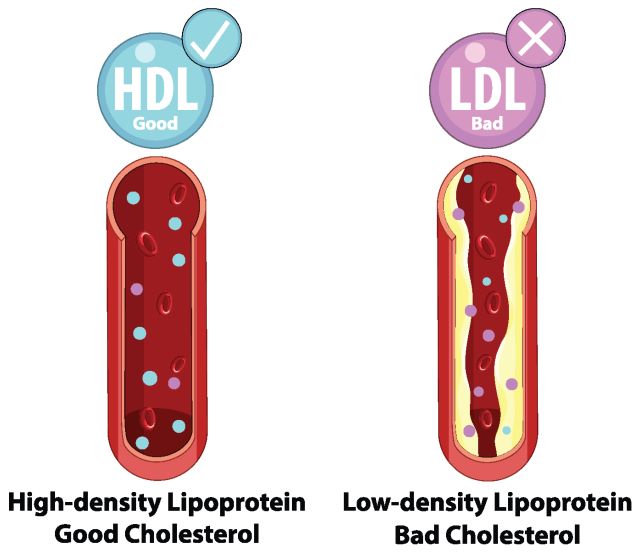

Herz-Kreislauf-Erkrankungen: Lipoproteine – genauere Marker für Risikoeinschätzung